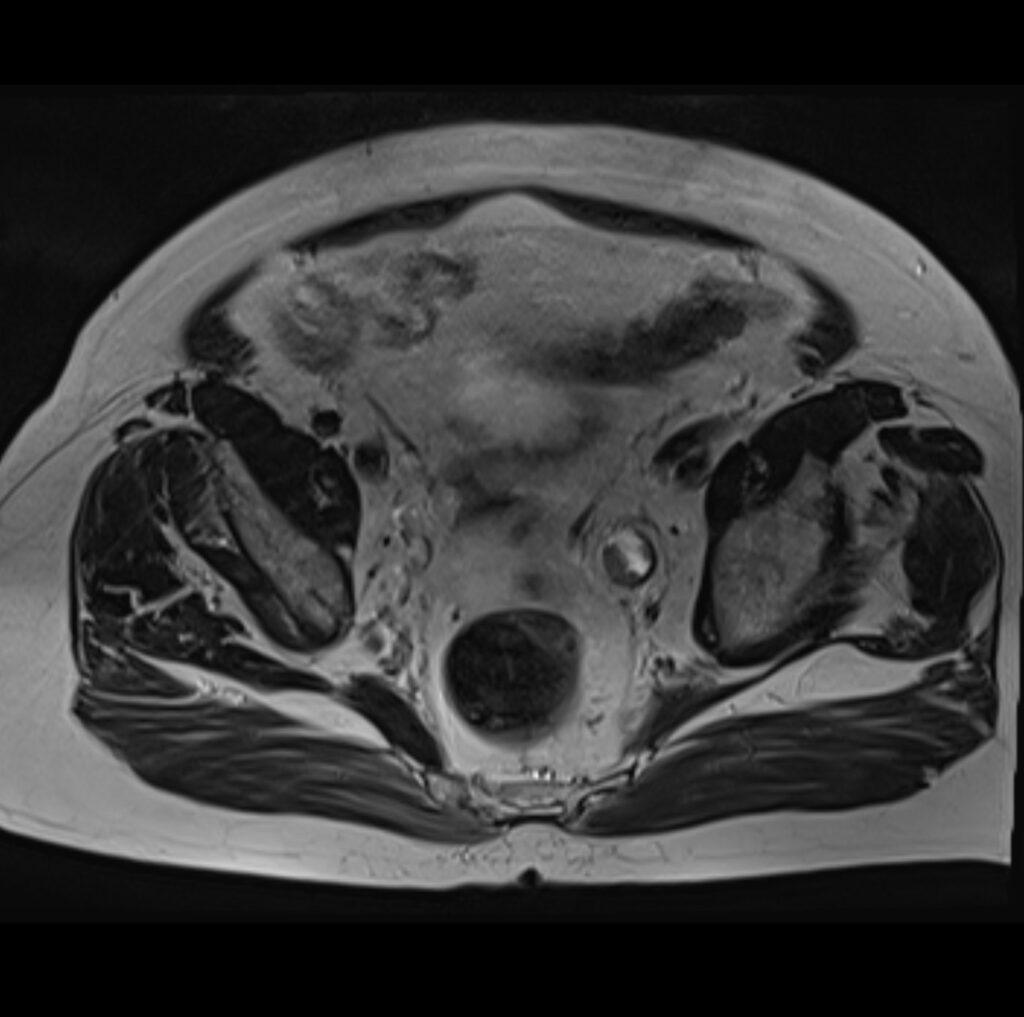

MR images revealed the left dilated ureter and intraluminal polypoidal masses at its distal segment. Associated moderate left hydronephrosis is noted.